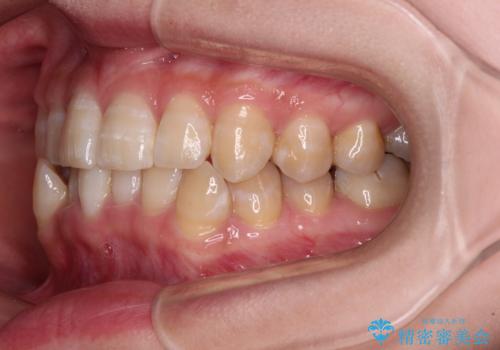

- 下顎の八重歯を気にして来院された患者様です。

マウスピース矯正でもワイヤー矯正でも対応可能であり、マウスピースによる治療を希望されたため、インビザラインを用いることとしました。

下顎前歯にデコボコが集中していたため、顎間ゴムによる後方移動とIPR(歯と歯の間を削ること)により歯列を整えることとしました。

下顎前歯のデコボコが集中しており、奥歯の咬み合わせは、上顎に対して下顎が前方位にある状態でした。下顎の歯列を後方へ移動させる治療はインビザラインの得意とするところですので、1年程度で無事に治療を終えることができました。